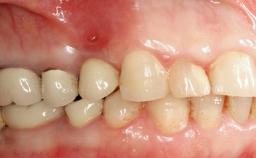

A 47-year-old woman who had suffered from aggressive periodontitis requiring a number of periodontal interventions over more than 10 years was referred by her general dental practitioner and periodontologist for bone augmentation and implant therapy. Her failing dentition had already been scheduled for extraction. The patient expressed a desire for implant-supported fixed restorations and esthetic improvement of her lower face. She had agreed to consult with a maxillofacial surgeon after the referring dentist had suggested bone augmentation. An initial examination by the maxillofacial surgeon revealed mobility of all residual teeth in a patient who was very unhappy with the function of her removable partial dentures. Due to periodontally migrated flaring teeth and loss of occlusal support, the vertical dimension of occlusion was dramatically reduced. The patient was displeased with her lower face because of deepened nasolabial, commissural, and supramental folds.